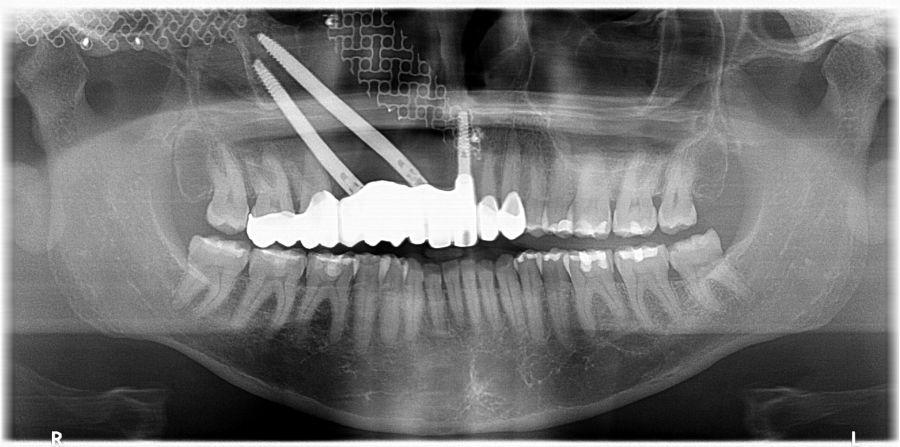

El día de la colocación de las estructuras, se arenó el interior de las coronas dentosoportadas con óxido de aluminio de 50 m y fueron cementadas con cemento de resina Multilink Ò. El puente implantosoportado se atornilló al torque indicado (20Nw) (Figuras 14, 15, 16 y 17).

En enero de 2021, el puente implantosoportado fue atornillado con un torque controlado (20 Nw), y las coronas dentosoportadas cementadas con éxito. La paciente refirió una notable mejoría en la función masticatoria, fonación y estética facial, manifestando un alto grado de satisfacción.

En el seguimiento a 4 años tras la colocación de la prótesis definitiva, no se observaron complicaciones mecánicas ni biológicas. La paciente continúa libre de enfermedad y con una correcta adaptación al tratamiento rehabilitador implantosoportado (Figura 18).